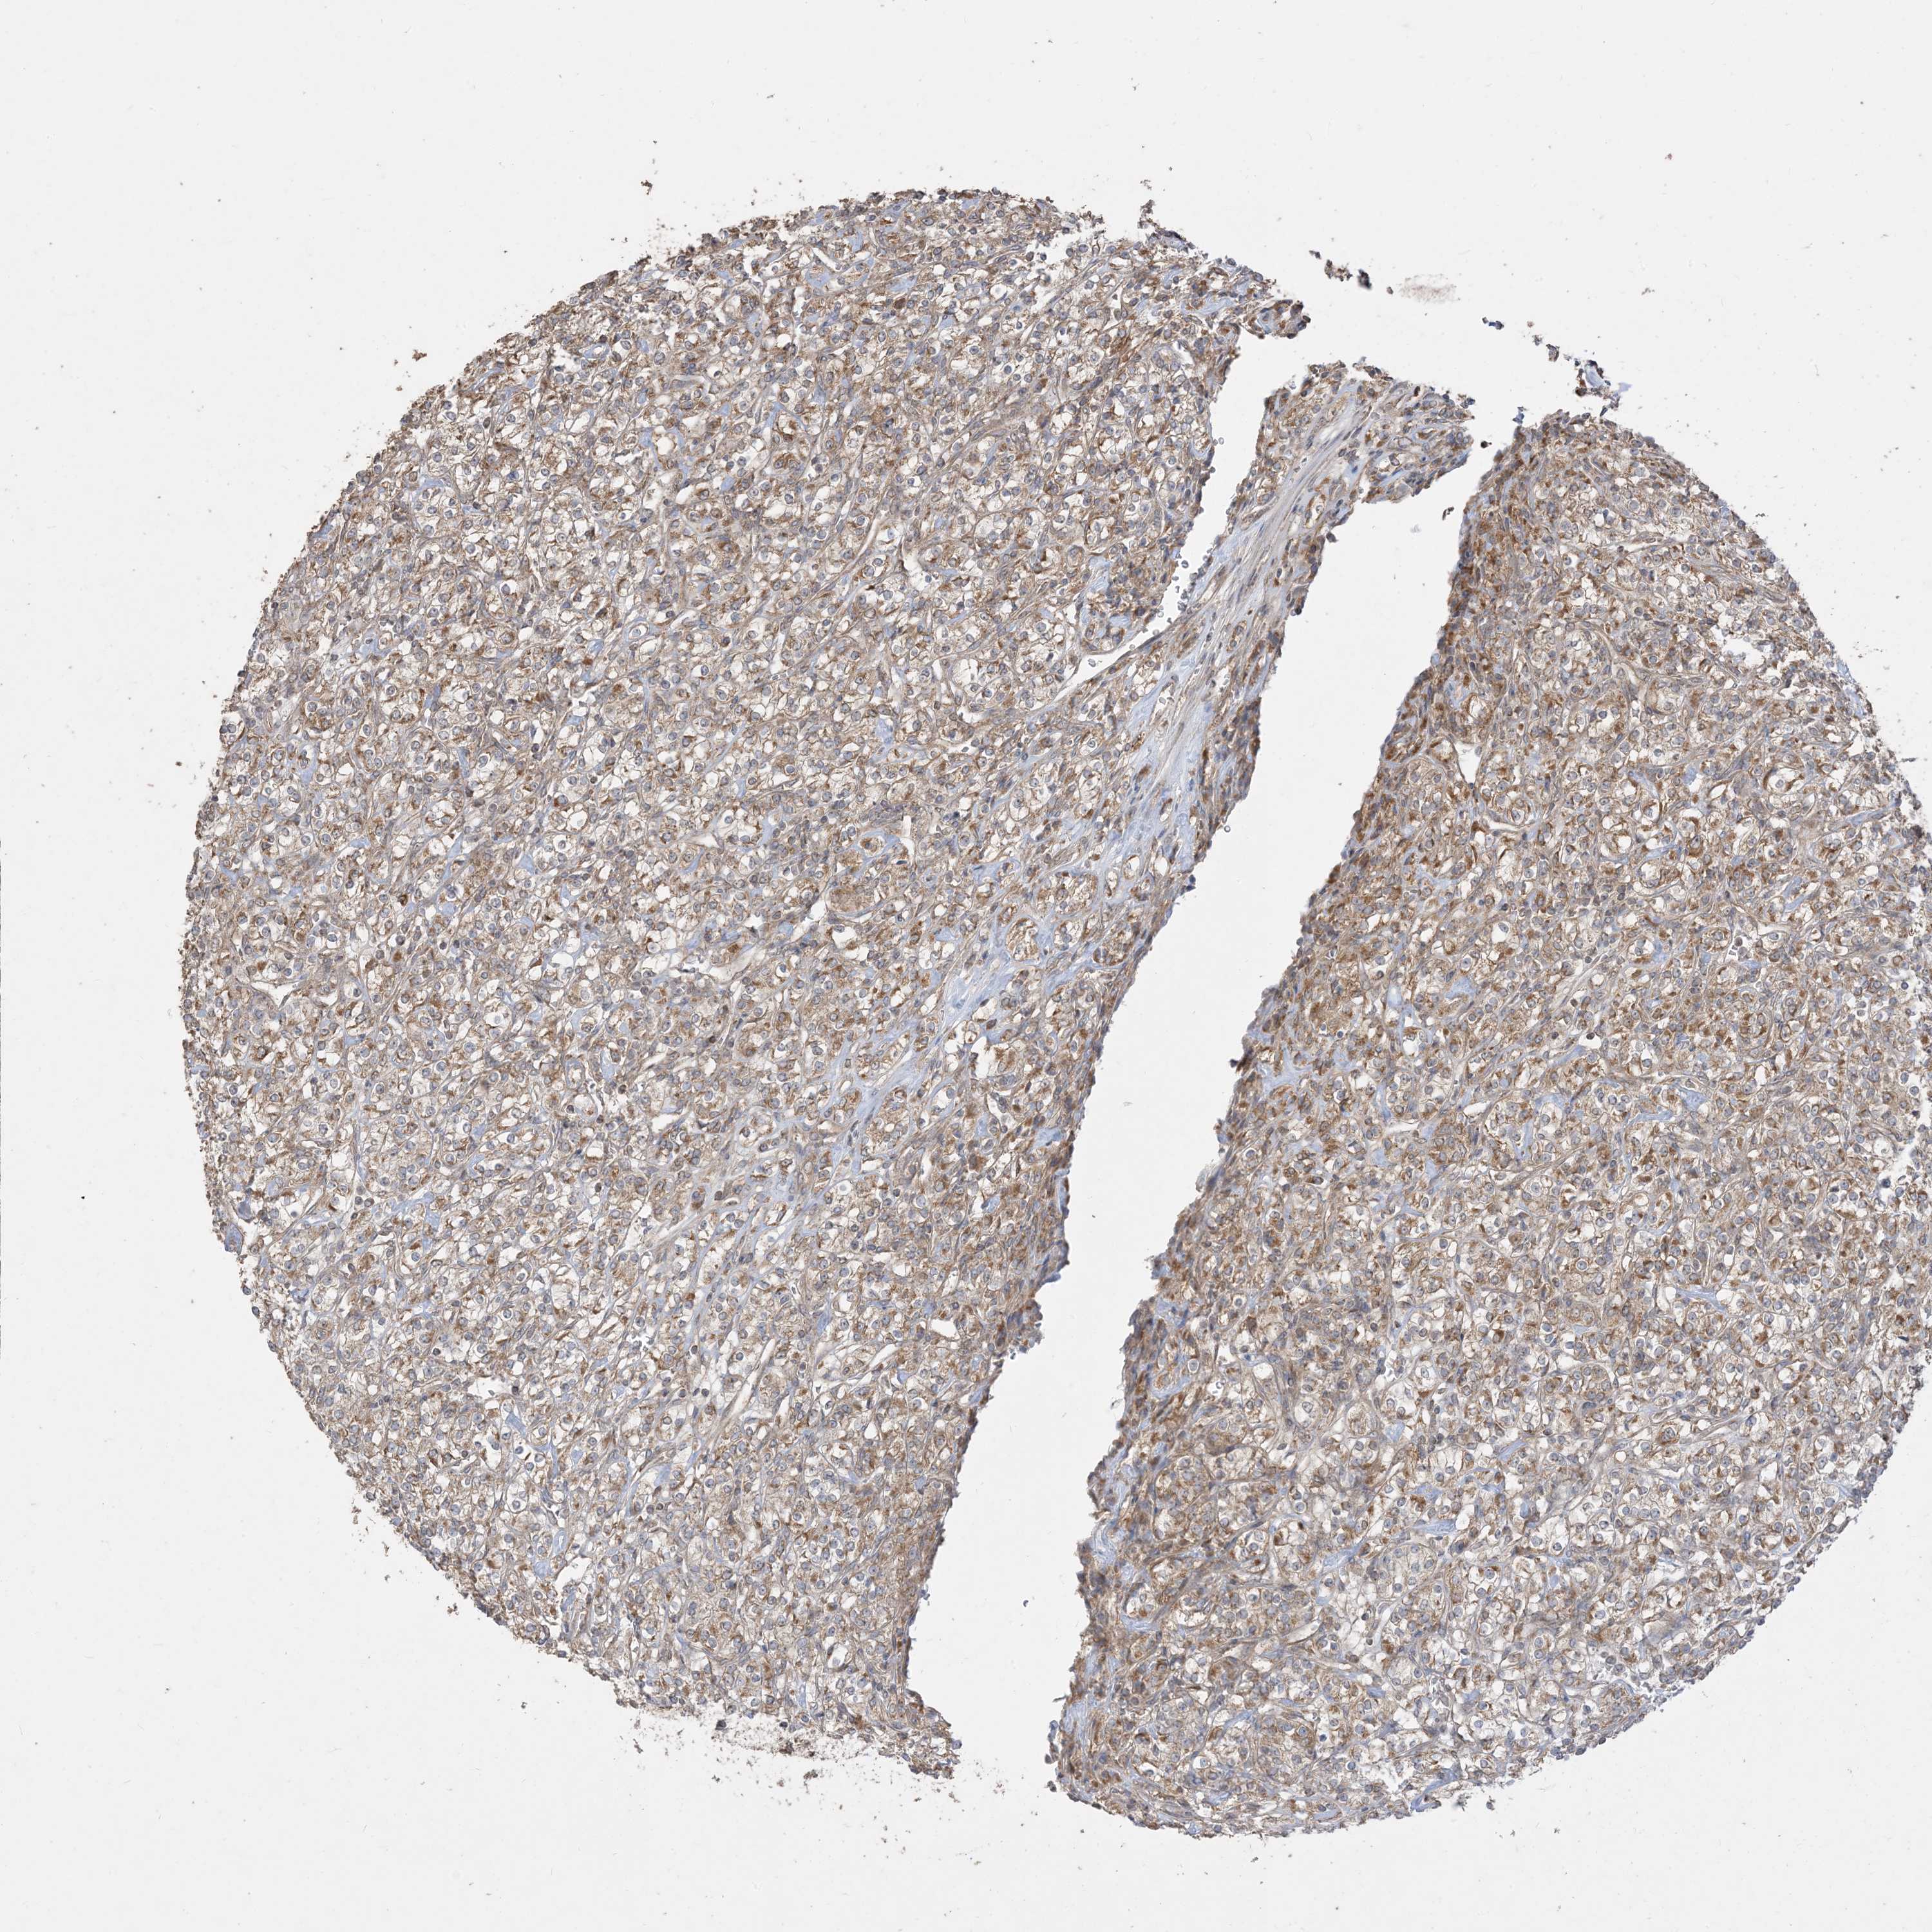

KIDNEY RENAL CLEAR CELL CARCINOMA (VALIDATION) - Interactive survival scatter ploti

The Survival Scatter plot shows the clinical status (i.e. dead or alive) for all individuals in the patient cohort, based on the same data that underlies the corresponding Kaplan-Meier plots. Patients that are alive at last time for follow-up are shown in blue and patients who have died during the study are shown in red.

The x-axis shows the expression levels (FPKM) of the investigated gene in the tumor tissue at the time of diagnosis. The y-axis shows the follow-up time after diagnosis (years). Both axes are complimented with kernel density curves demonstrating the data density over the axes. The top density plot shows the expression levels (FPKM) distribution among dead (red) and alive patients (blue). The right density plot shows the data density of the survived years of dead patients with high and low expression levels respectively, stratified using the cutoff indicated by the vertical dashed line through the Survival Scatter plot. This cutoff is automatically defined based on the FPKM cutoff that minimizes the p-score. The cutoff can be changed by dragging the vertical line or by entering a cutoff value in the square labeled "Current cut-off".

Under the Survival Scatter plot the p-score landscape (black curve; left axis) is shown together with dead median separation (red curve; right axis). Dead median separation is the difference in median mRNA expression between patients who have died with high and low expression, respectively. It is calculated as follows: median FPKM expression of dead patients with high expression - median FPKM expression of dead patients with low expression. This is intended to aid the user in visually exploring custom cutoffs and the associated p-scores and dead median separation.

Individual patient data is displayed and can be filtered by clicking on one or more of the category buttons on the top of the page. Categories describing expression level and patient information include: high, low, alive, dead, female, male and tumor stages. The scale of the x-axis can be toggled between linear and log-scale by clicking on the "x log" button. Mouse-over function shows TCGA ID, patient information and mRNA expression (FPKM) for each patient.

& Survival analysisi

Kaplan-Meier plots summarize results from analysis of correlation between mRNA expression level and patient survival. Patients were divided based on level of expression into one of the two groups "low" (under cut off) or "high" (over cut off). X-axis shows time for survival (years) and y-axis shows the probability of survival, where 1.0 corresponds to 100 percent.

SIRT3 is not prognostic in Kidney Renal Clear Cell Carcinoma (validation)

: 17.16

Average pTPM 16.1

Number of samples 100